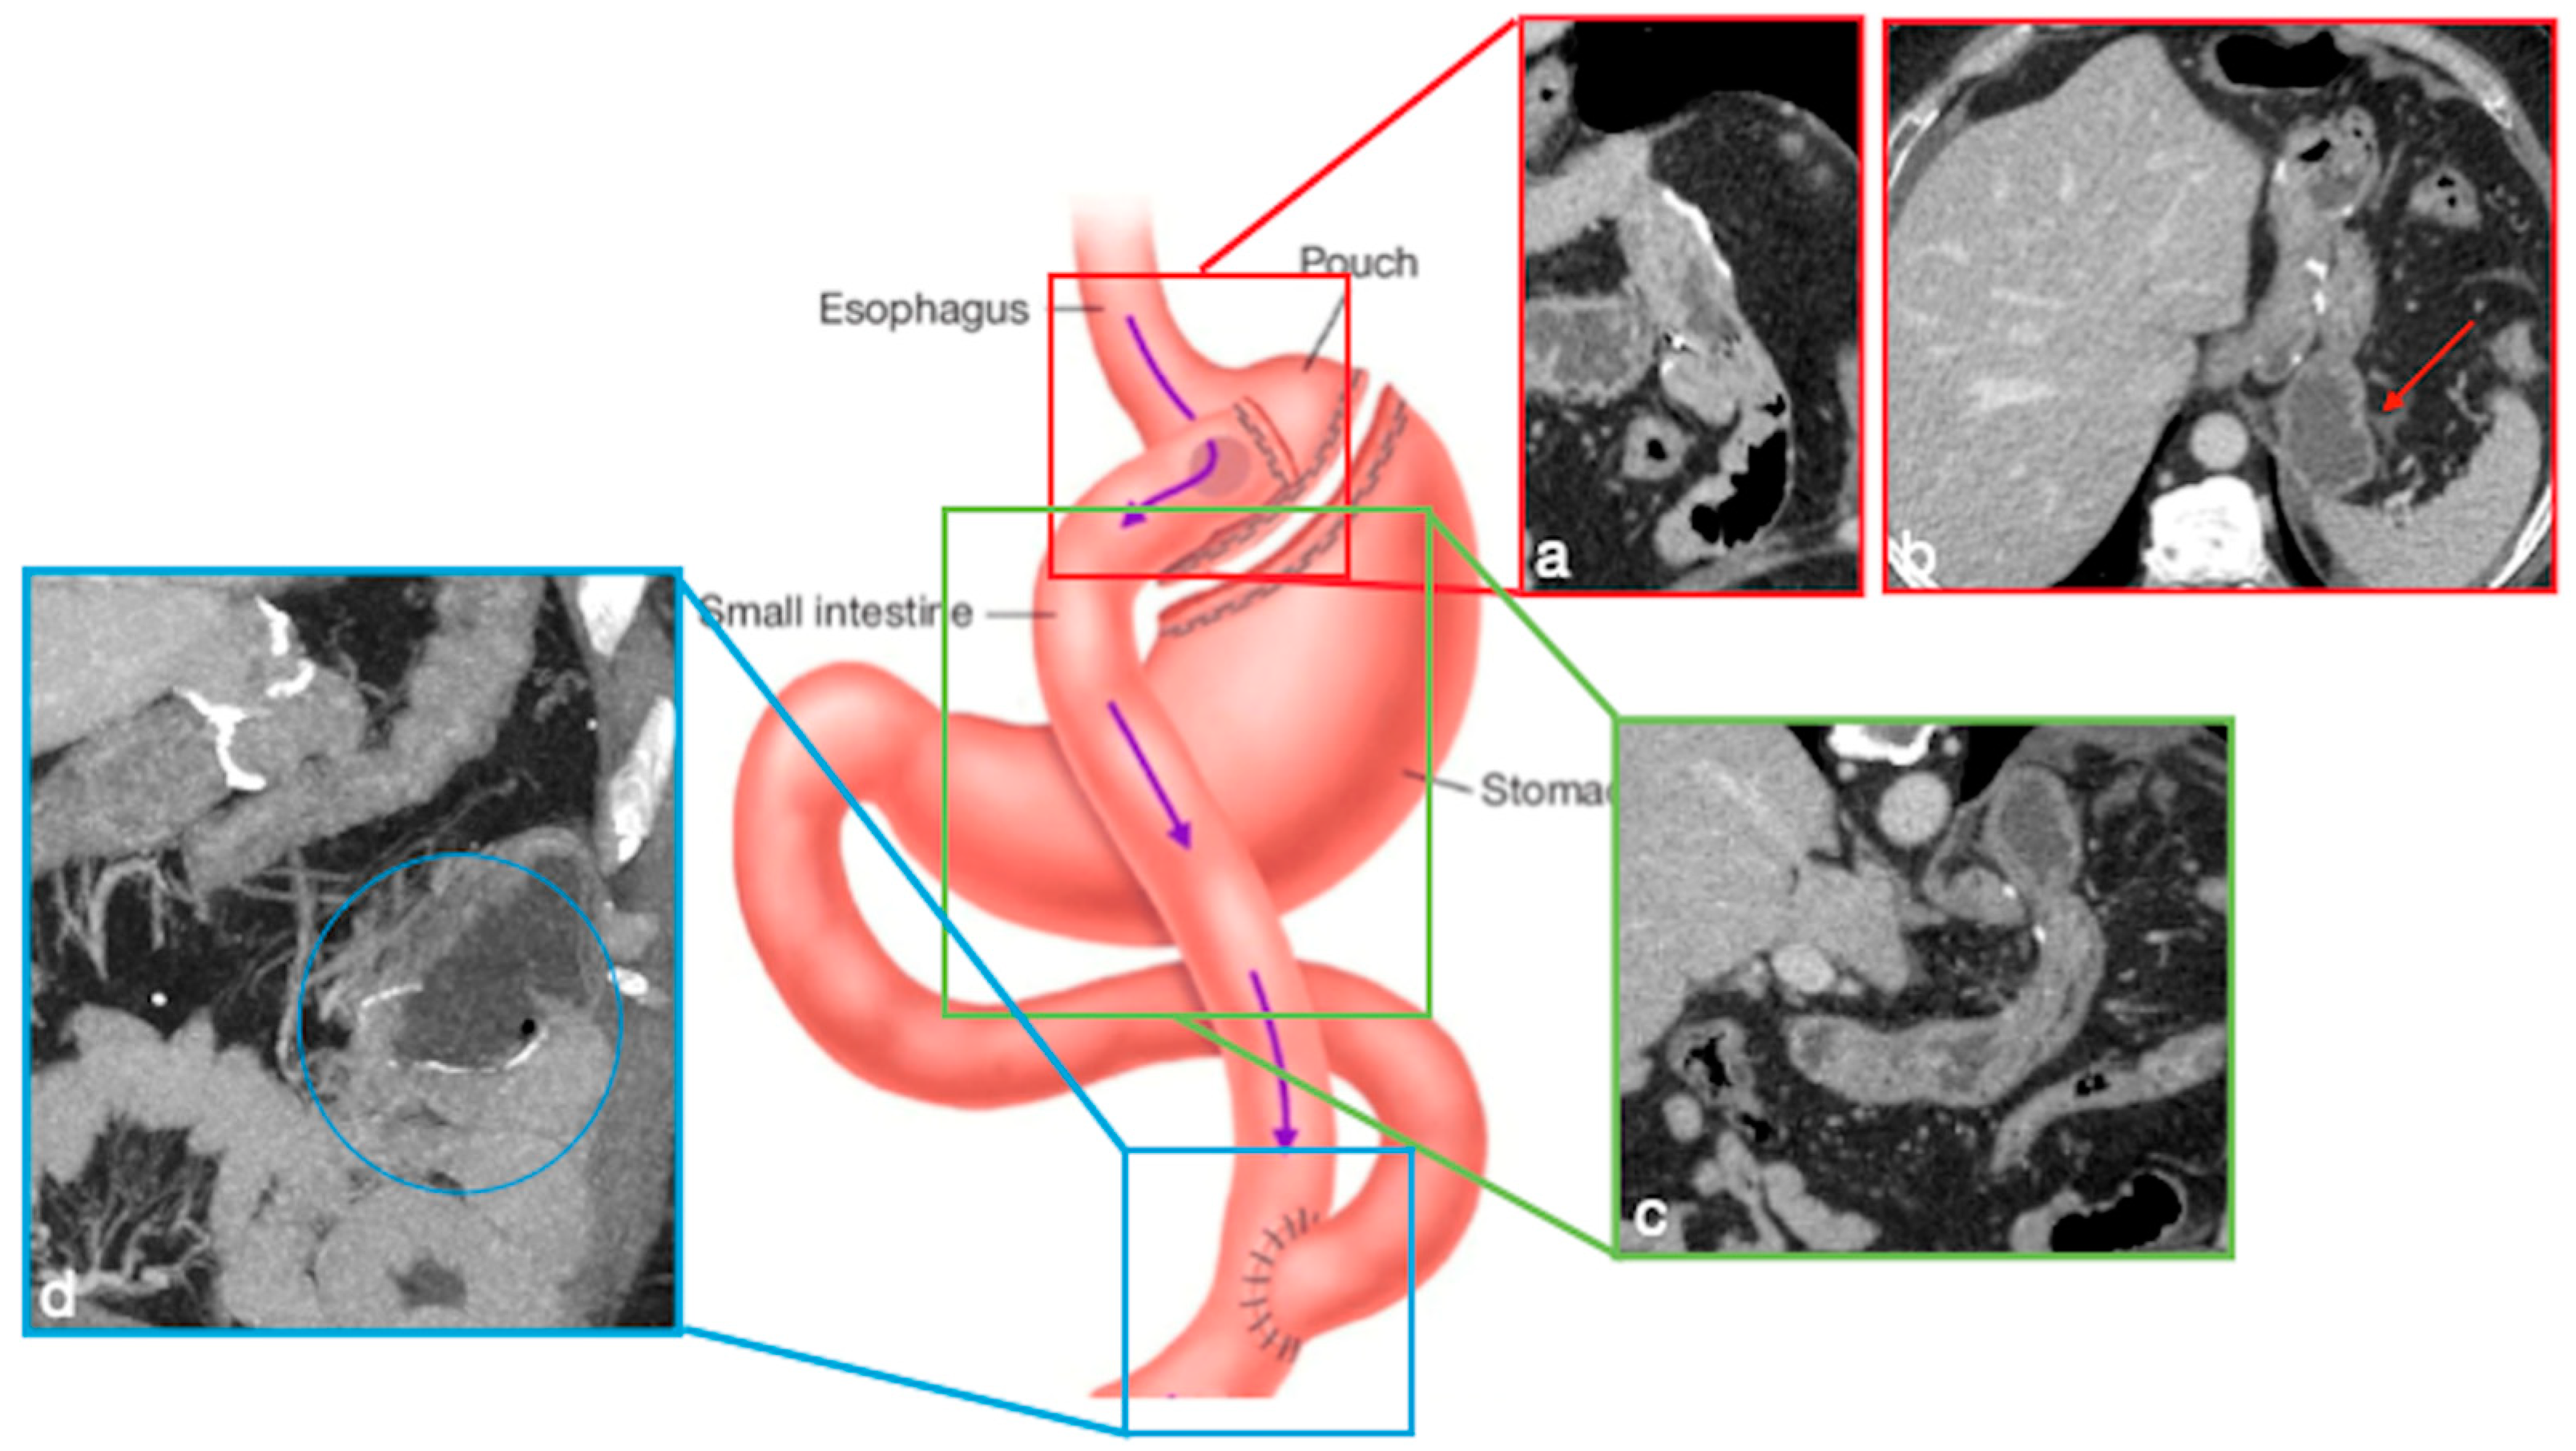

Figure 6. Mini-gastric bypass. Surgical sutures seen at CT. Gastric pouch (a,b, coronal view (a) and MIP (b) straight arrows). Bypassed stomach (a,b, curved arrows). Gastrojejunostomy (c, coronal oblique view). The scheme was adapted from https://www.theossi.com/mini-gastric-bypass-obesity-surgery.html (accessed on 23 October 2022).

In OAGB-MGB an endo-stapler (from the His angle to 2 cm proximal to the pylorus) is used to create a mini-gastric tube, which is connected with the jejunum via a side-to-side antecolically anastomosis, in order to bypass gastric antrum, duodenum, and proximal jejunum (Figure 6) [16]. The goal of the gastric pouch is to remove the reservoir function of the stomach and convert the stomach into a nonobstructed extension of the esophagus, where food does not stay in a reservoir but is dumped into the lumen of the jejunum. The presence of gastrojejunostomy causes malabsorption [16,17].